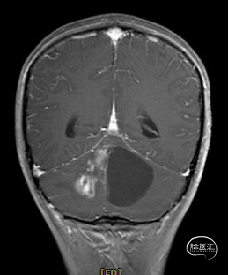

术前MRI

术后MRI